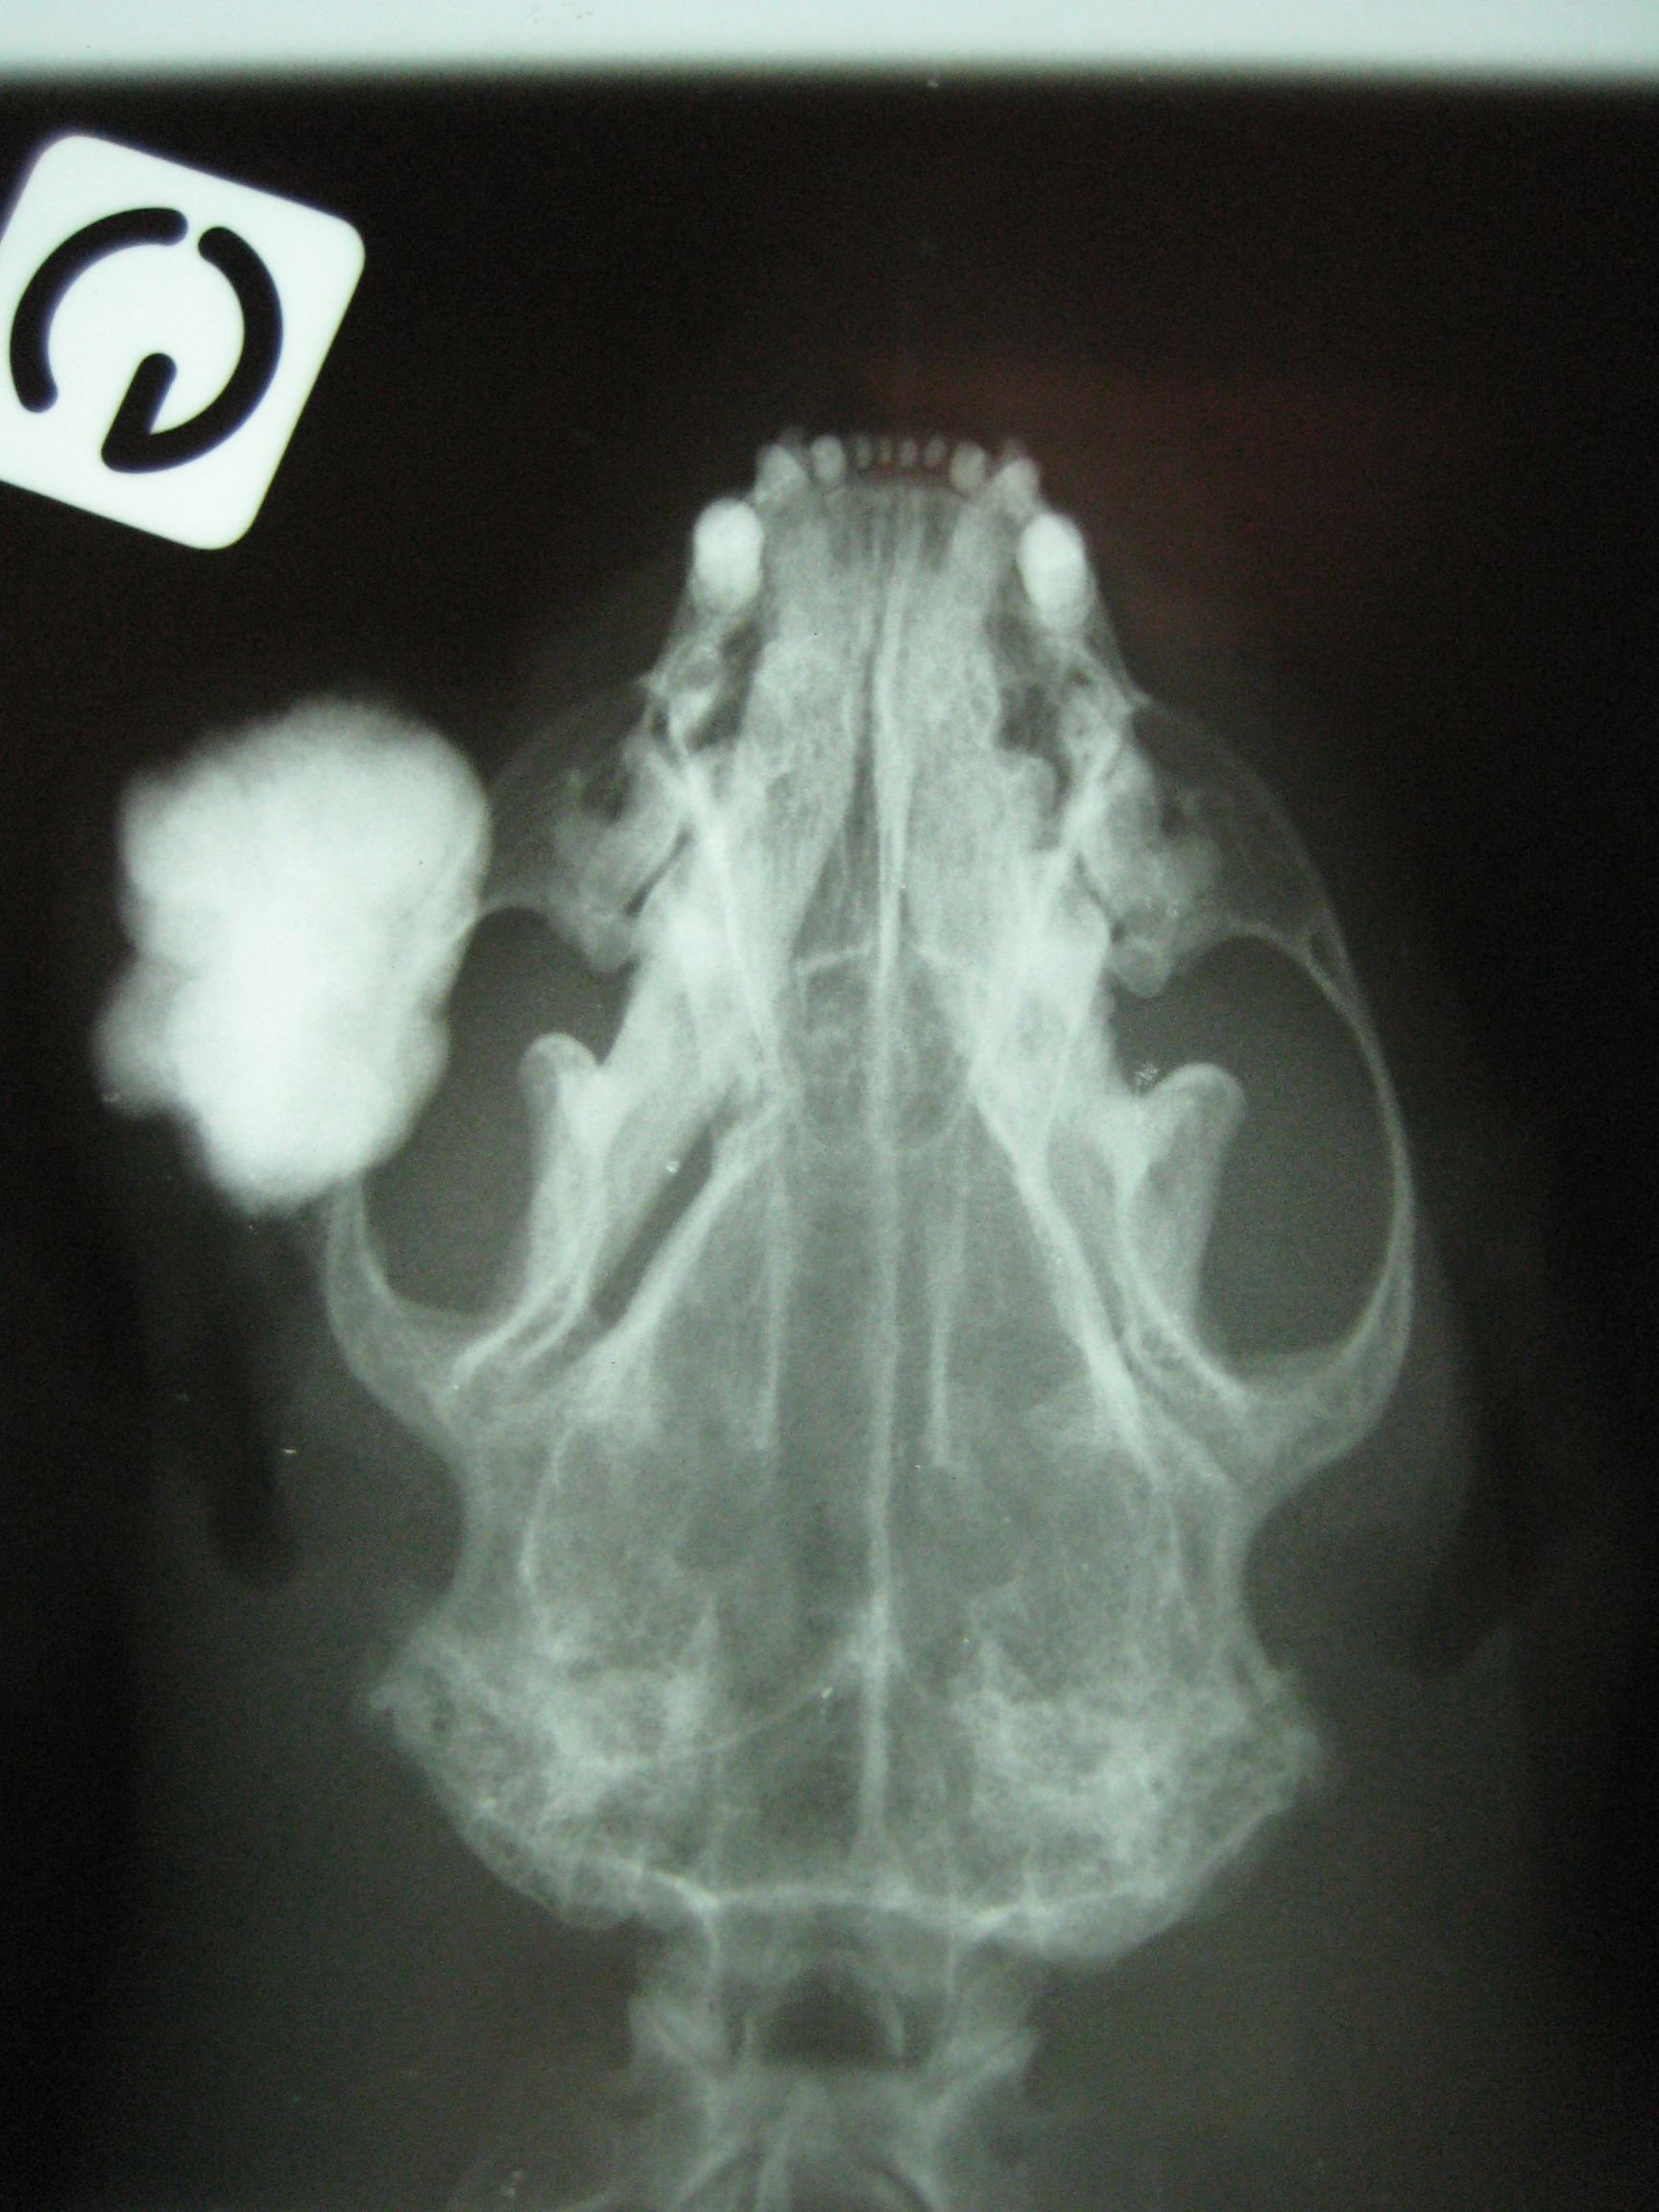

Pour diagnostiquer et classifier une tumeur, il faut a minima un examen cytologique ou histologique sur un prélèvement réalisé en chirurgie. Un bilan d'extension par radiographie, échographie et/ou scanner est recommandé de manière générale, pour vérifier la présence de métastases. Cela permet également de planifier une chirurgie au besoin et d'adapter le traitement post-opératoire.

Les furets présentent des maladies cardiaques, en particulier lorsqu'ils sont âgés de plus de 5 ans. On recommande des visites de routine avec un examen échocardiographique afin de déceler d'éventuelle anomalie le plus précocement possible. En cas de signes cliniques, les furets sont souvent abattus et présentent des signes de détresse respiratoire. Une radiographie permettra de mettre en évidence les premiers signes de maladie cardiaque mais une échocardiographie réalisée par un vétérinaire expérimenté reste nécessaire pour confirmer le diagnostic. Le traitement fait appel à des médicaments cardiaques.